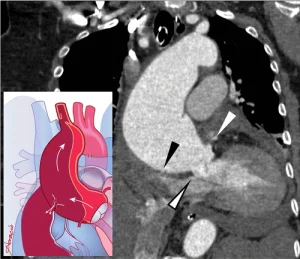

Hình 3a. Bóc tách động mạch chủ cấp (AAD) và hội chứng động mạch chủ cấp (AASs) khác.

(a) Bóc tách động mạch chủ cấp ở bệnh nhân nam 74 tuổi đột ngột đau ngực dữ dội, bắt đầu lan ra sau lưng và bụng, sau đó là khó thở tiến triển. Chụp CT mạch máu mặt phẳng coronal ở ngang mức động mạch chủ lên cho thấy tổn thương động mạch chủ cấp tính type A Stanford với lá nội mạc bóc tách kéo dài từ gốc động mạch chủ (đầu mũi tên đen) đến quai động mạch chủ, bóc tách động mạch thân cánh tay đầu và lan rộng vào động mạch chủ xuống và động mạch chủ bụng (không hiển thị). Có máu tụ lớn và bao quanh lớp ngoại mạc chèn ép động mạch phổi chính (main pulmonary artery) (đầu mũi tên trắng) và lan rộng đến các động mạch phổi gần rốn phổi (central pulmonary arteries). Lòng thật (T) bị chèn ép bởi lòng giả dọc theo đoạn cong nhỏ hơn (đoạn đầu) của quai động mạch chủ và lá nội mạc bóc tách cho thấy hiện tượng ảnh giả do chuyển động gây mờ (blurring motion artifact).